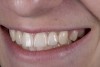

(21.) Smile view.

Figure 21

When the patient returned, the fit was evaluated in the mouth. Once verified, the internal surface of the framework was etched with a 9.5% hydrofluoric acid for 90 seconds and then salinized. After etching the enamel surface with phosphoric acid for 30 seconds and applying the primer (Single Bond Plus, 3M ESPE) to both the internal surface of the framework and the enamel, the zirconia bridge was bonded with a dual-cure resin cement (RelyX™ ARC, 3M ESPE). After the procedure, the patient ended up with a long-term, high-strength esthetic restoration advantaged by the bonding potential of fledspathic ceramic (Figure 20 through Figure 24). Six years after placement, the prosthesis had remained in place with no complications.